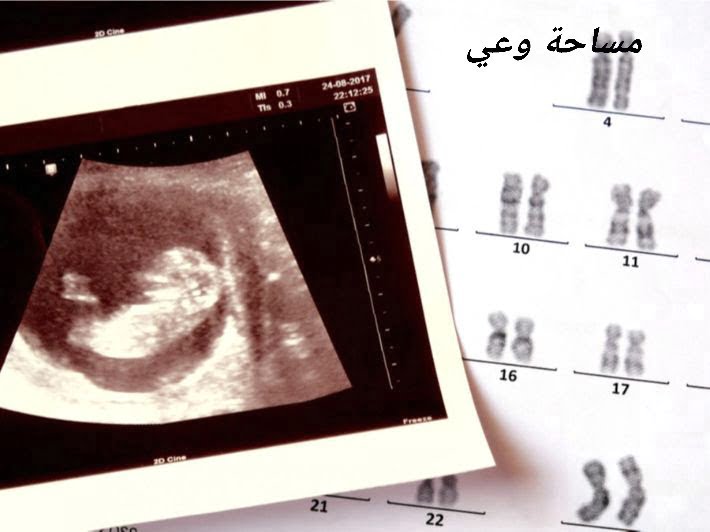

أسباب وأعراض متلازمة داون من أهم الأمور التي يتم البحث عنها عبر محركات البحث المختلفة، حيث تمثل هذه المتلازمة مجموعة متنوعة من الاضطرابات الجسدية والنفسية التي تحدث بسبب وجود مشكلة في الجينات خلال فترة الحمل، حيث إن أغلب الأطفال المصابين بمتلازمة داون يشتركون في نفس الأعراض إلا أنه من الممكن أن تختلف شدة هذه الأعراض […]